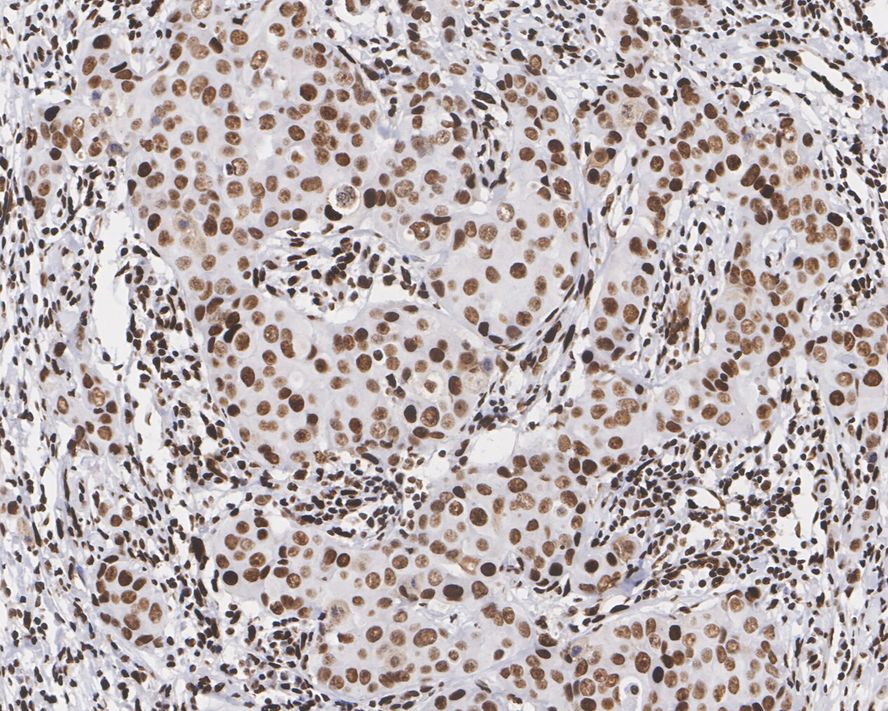

Immunohistochemical analysis of paraffin-embedded human breast carcinoma tissue with Rabbit anti-PML Protein antibody (HA750843) at 1/1,000 dilution.

The section was pre-treated using heat mediated antigen retrieval with sodium citrate buffer (pH 6.0) (high pressure) for 2 minutes. The tissues were blocked in 1% BSA for 20 minutes at room temperature, washed with ddH2O and PBS, and then probed with the primary antibody (HA750843) at 1/1,000 dilution for 1 hour at room temperature. The detection was performed using an HRP conjugated compact polymer system. DAB was used as the chromogen. Tissues were counterstained with hematoxylin and mounted with DPX.